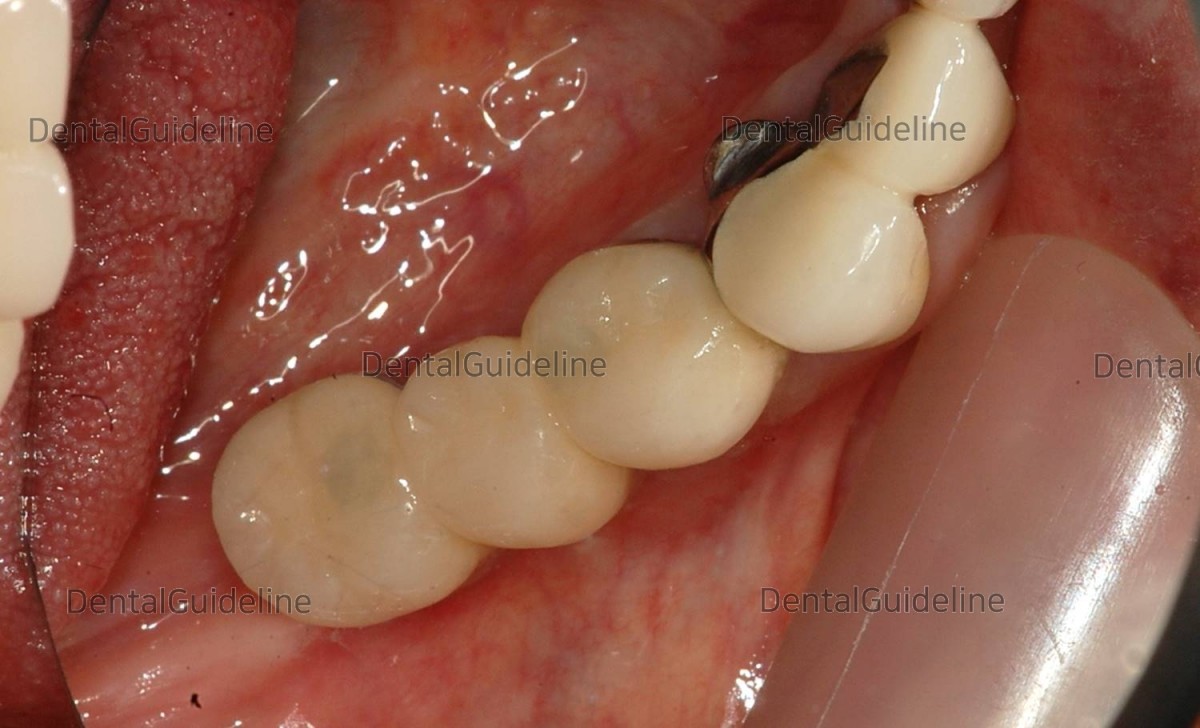

1 month after the implant surgery

in the right mandible. Intraoral photo after anesthesia on the day of implant

surgery in the left mandible.

had a longer wait than usual. This photo is 6 months after implantation. photo before 2nd surgery.![]()

As expected from CBCT, the

remaining alveolar bone on the outside was thin.

An additional GBR was

performed. (xenograft-even after years, the grafted bone has the lowest resorption.)